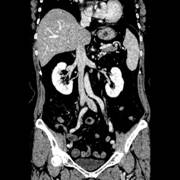

VHSは、CT検査の寝台(テーブル)がノンストップで連続往復しながら撮影し、経時的なデータを収集していく新しいテクノロジーです。

Volume Helical Shuttle(以下VHS)によるCT撮影は、テーブルスピードが安定するまで の加速時ならびにテーブルが停止するまでの 減速時のデータも画像化できるため、無駄な被ばくを軽減するだけでなく、4D画像の時間 分解能が向上し、30cm以上の広範囲における4D画像も容易に得ることが可能です。

また、4次元撮影や機能診断は撮影回数が従来に比べ増加するため、被ばく増加が大きな壁となり、撮影することは困難でしたが、逐次近似法を用いたノイズ低減処理技術を使用することにより、被ばくを大幅に削減できます。